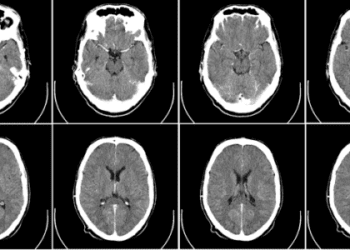

1. When used for the selection of patients with stroke for intravenous thrombolysis within 3 hours of symptom onset, computed tomography ...